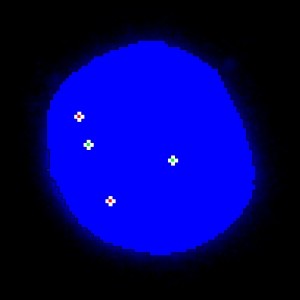

To determine the HER2/CEN-17 ratio, the total number of HER2 signals (Red) and the number of CEN-17 (Green) signals in the same 20 nuclei are identified. The total number of HER2 signals is then divided by the number of CEN-17 signals. Ratios above 2 are classified as amplified whereas ratios below 2 are classified un-amplified. Caution should be taken when intepreting on results near the cut-off (1.8 – 2.2). The operator only needs to define an overall region of interest.

The image analysis algorithm for this protocol involves several steps. First, a pre-processing step identifies the stained nuclei and the gene probes. Nuclei exhibiting signals of only one color are then removed.